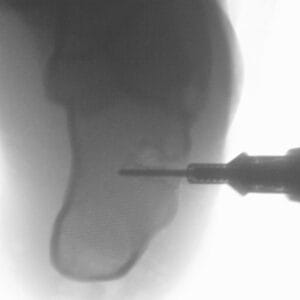

| Pathology | Pes Cavus |

| Procedure | Cole Osteotomy, Dwyer, Lateralizing Calcaneal Osteotomy, Metatarsal Dorsiflexion Osteotomy |

| Area | Midfoot |

Pes Cavus – Bone Model